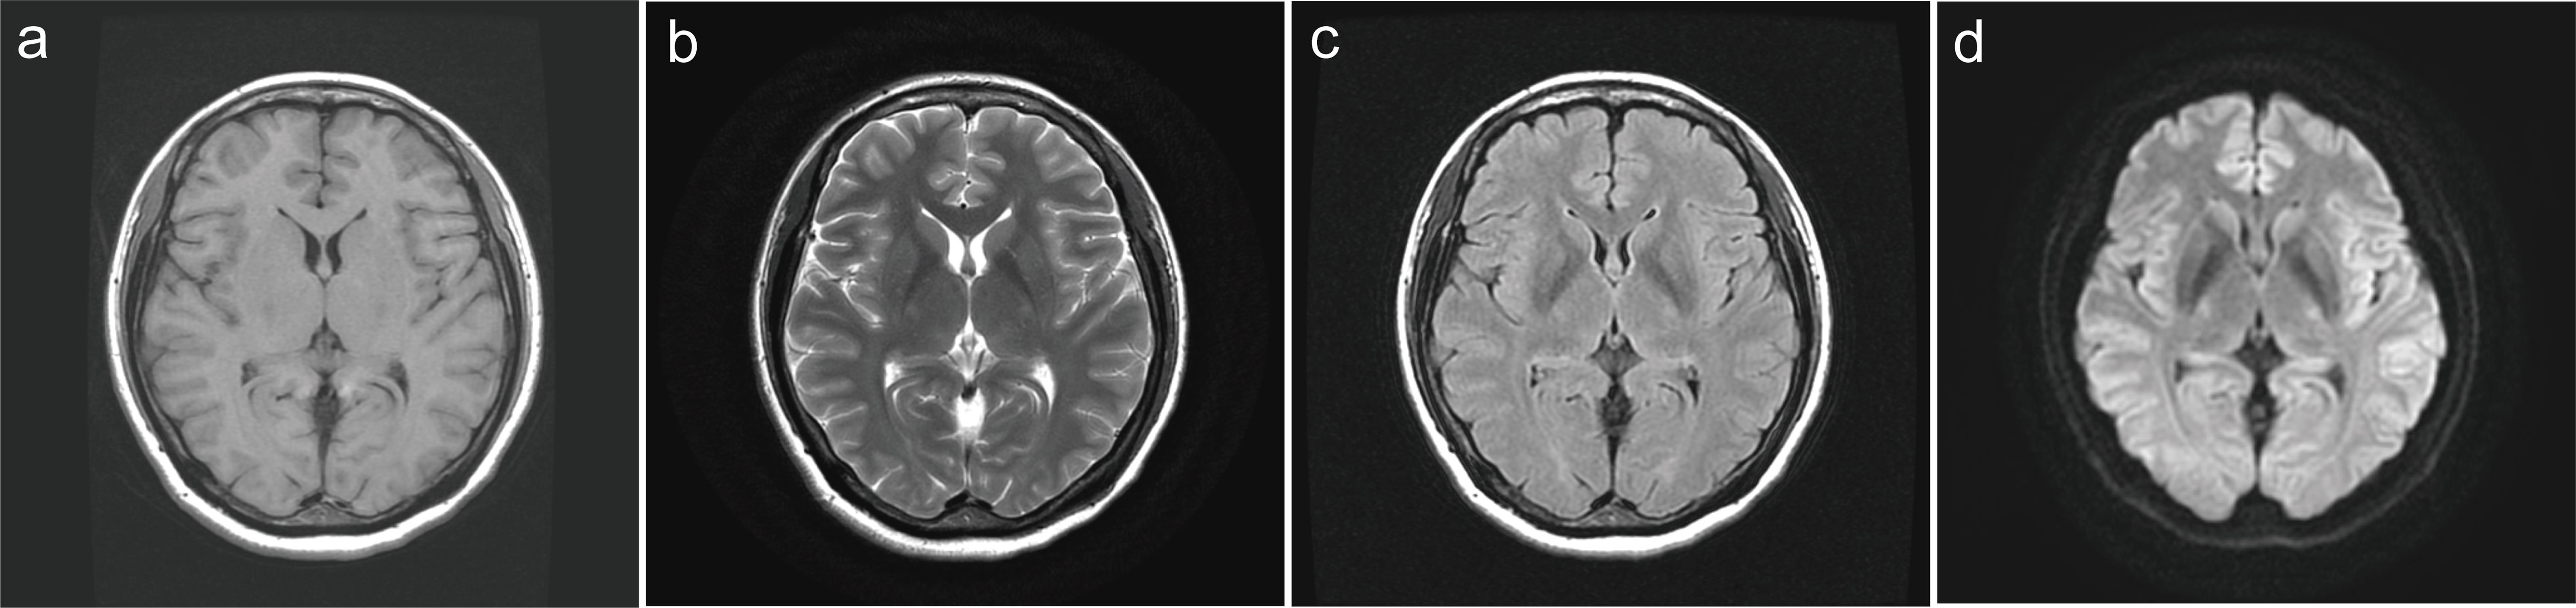

The patient had a score of 26 on the Insomnia Severity Index (ISI), indicating severe clinical insomnia, and a score of 19 on the Pittsburgh Sleep Quality Index (PSQI), indicating poor sleep quality. There were no anomalies discovered during the physical checkup. No abnormalities were found in routine blood and urine tests, or liver and renal function tests. No abnormalities were found on a chest X-ray, electrocardiogram, ultrasonogram (abdomen, thyroid, and breast), or cranial MRI (Fig. 1).

Cranial magnetic resonance routine scan images.

Fig. 1  Cranial magnetic resonance routine scan images.

(a) T1-weighted image, (b) T2-weighted image, (c) T2-weighted-fluid-attenuated inversion recovery image, (d) diffusion-weighted image.